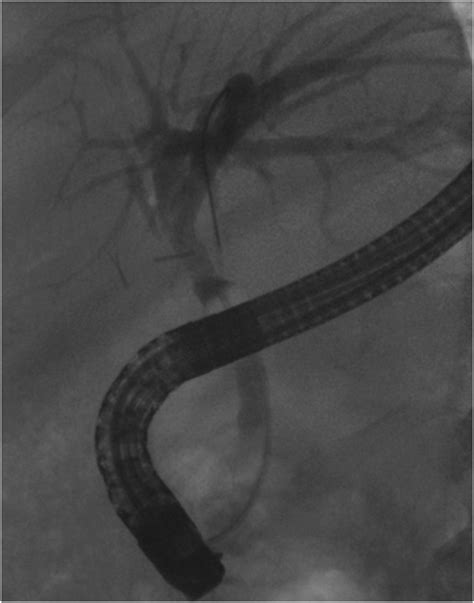

These devices are primarily inserted via a procedure known as Endoscopic Retrograde Cholangiopancreatography (ERCP). During this minimally invasive procedure, a gastroenterologist uses an endoscope—a flexible, lighted tube with a camera—to navigate through the esophagus and stomach into the small intestine, reaching the opening of the bile duct to deploy the stent.

• Imaging: Using fluoroscopy (real-time X-ray), the doctor identifies the exact location of the blockage.

• Deployment: Once the location is identified, the stent is advanced through the endoscope and expanded within the narrowed area of the bile duct.